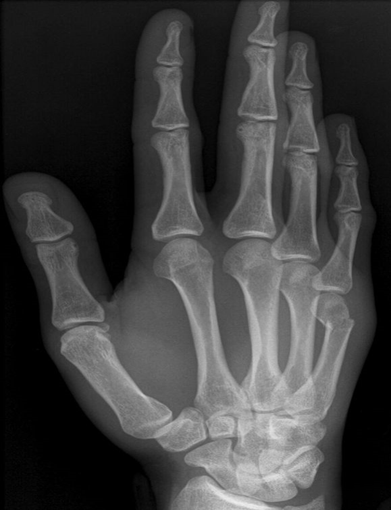

(9)Rolando 骨折

纵向暴力导致第一掌骨基底部劈裂骨折。属于关节内骨折。